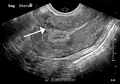

A very large (9 cm) fibroid of the uterus which is causing pelvic congestion syndrome as seen on ultrasound

A small uterine fibroid seen within the wall of the myometrium on a cross-sectional ultrasound view- Two calcified fibroids (in the uterus)